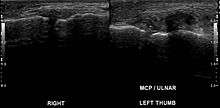

A Stener lesion is a type of traumatic injury to the thumb. It occurs when the aponeurosis of the adductor pollicis muscle becomes interposed between the ruptured ulnar collateral ligament (UCL) of the thumb and its site of insertion at the base of the proximal phalanx. No longer in contact with its insertion site, the UCL cannot spontaneously heal.[1]

In 1962, Bertil Stener described a lesion which he observed to occur in a subset of patients suffering from gamekeeper's thumb. In these patients, the distal attachment of the UCL was traumatically avulsed from its site of insertion at the base of the proximal phalanx of the thumb. The severed end of the ligament would become trapped under the aponeurosis of the adductor pollicis muscle and therefore be unable to return to its proper anatomic position. Consequently, the severed ligament would fold on itself and thus be prevented from healing and restoring stability to the MCP joint.[3]

For a Stener lesion to occur, both the proper and accessory collateral ligaments of the thumb must be completely ruptured. The Stener lesion is present in more than 80% of complete ruptures of the UCL of the thumb.